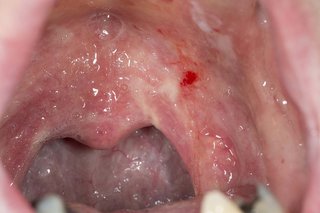

Cũng có thể đau nhiều hơn nếu như bạn nuốt hoặc nói chuyện. Họng hay amidal của bạn cũng có thể ửng đỏ lên.

Đôi khi, một mảng trắng hoặc một khoảng trắng có mủ sẽ hình thành trên amidal. Mảng trắng thường do nhiễm vi khuẩn Streptococcus hầu họng hơn là do nhiễm virus hầu họng.